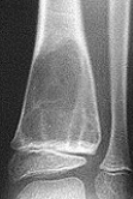

What disease is this? What does the arrow indicate? | Rheumatoid arthritis. Arrow = Bone erosion secondary to inflammation of retrocalcaneal bursa. |

What disease is this? | Gout |

What disease is this? What do the arrows indicate? | Gout Arrows = 'punched out' erosions |